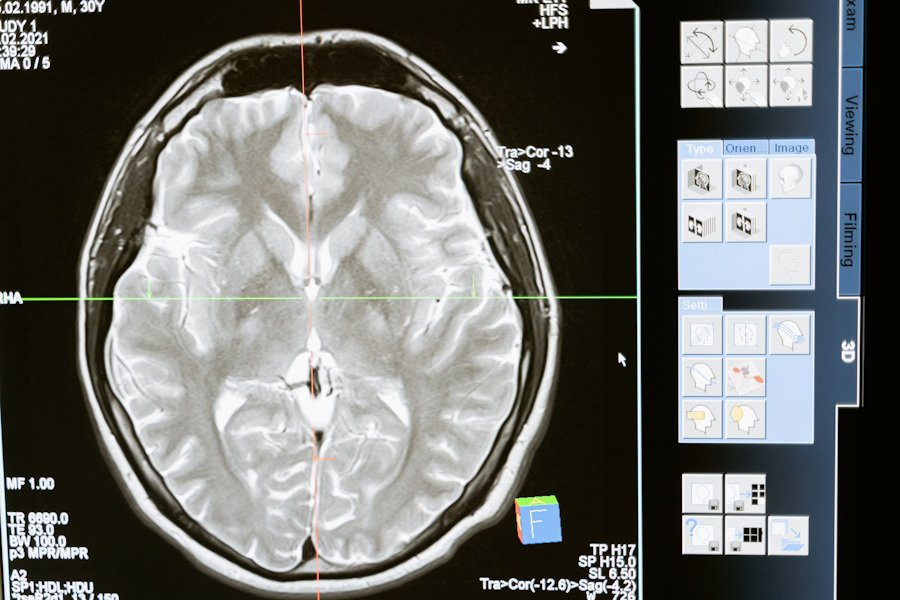

Закон Йеркса-Додсона, созданный еще в далеком прошлом, предполагает, что существует оптимальный уровень возбуждения для достижения наилучшей производительности мозга. Исследование использовало данные о возбуждении и производительности при принятии решений, связанных с восприятием.

В ходе исследования ученые получили перевернутую U-образную зависимость между возбуждением и производительностью при различных типах решений и сенсорных модальностях (визуальная, слуховой). Исследователи построили нейробиологически правдоподобную механистическую модель, подтверждающую эти результаты.

Ученые пришли к выводу, что перевернутая U-образная зависимость между возбуждением и производительностью является общим и устойчивым свойством сенсорной обработки, что открывает новые горизонты в понимании оптимальной работоспособности человеческого мозга.